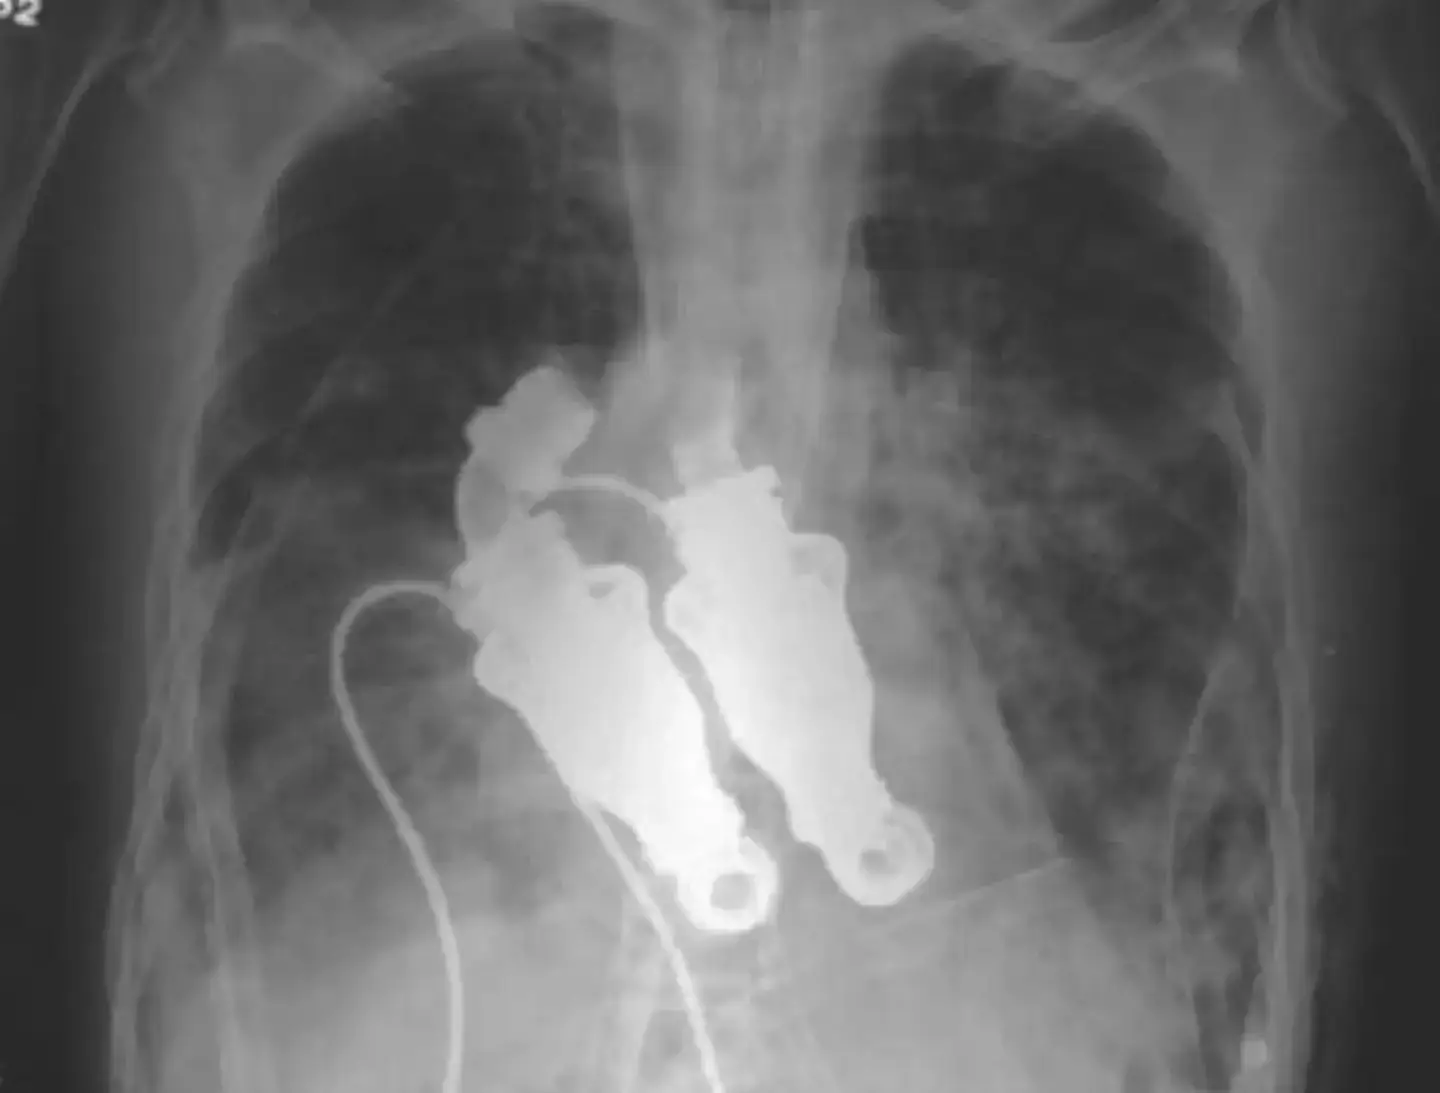

However, advancements in modern medicine reached a point in 2011 where two doctors at the Texas Heart Institute were able to create a device which used whirling rotors to pump blood around the human body without a heartbeat.

Dr. Billy Cohn and Dr. Buz Frazier first tested the idea in an eight-month-old calf called Abigail, removing her heart and successfully replacing it with two centrifugal pumps, which circulated the blood through her.

After practicing on 38 calves, Cohn and Frazier progressed to human trials – selecting a 55-year-old man called Craig Lewis, who was suffering from amyloidosis, a rare autoimmune disease that causes a build-up of abnormal proteins and, in turn, rapid heart, kidney and liver failure.

In March 2011, she approached Cohn and Frazier, who removed her husband’s heart and installed the artificial device.

Linda said: "I listened and it was a hum, which is amazing. He didn't have a pulse."

She said her husband – who worked for the city of Houston, maintaining the city’s vast system of wastewater pumps – would have appreciated the pulseless heart cobbled together from various materials, with Cohn explaining: "Dacron on the inside and fiberglass impregnated in silicone on the outside.

"There's a moderate amount of homemade stuff on here."

The doctors said the continuous-flow pump should last longer than other artificial hearts, and would cause fewer problems.